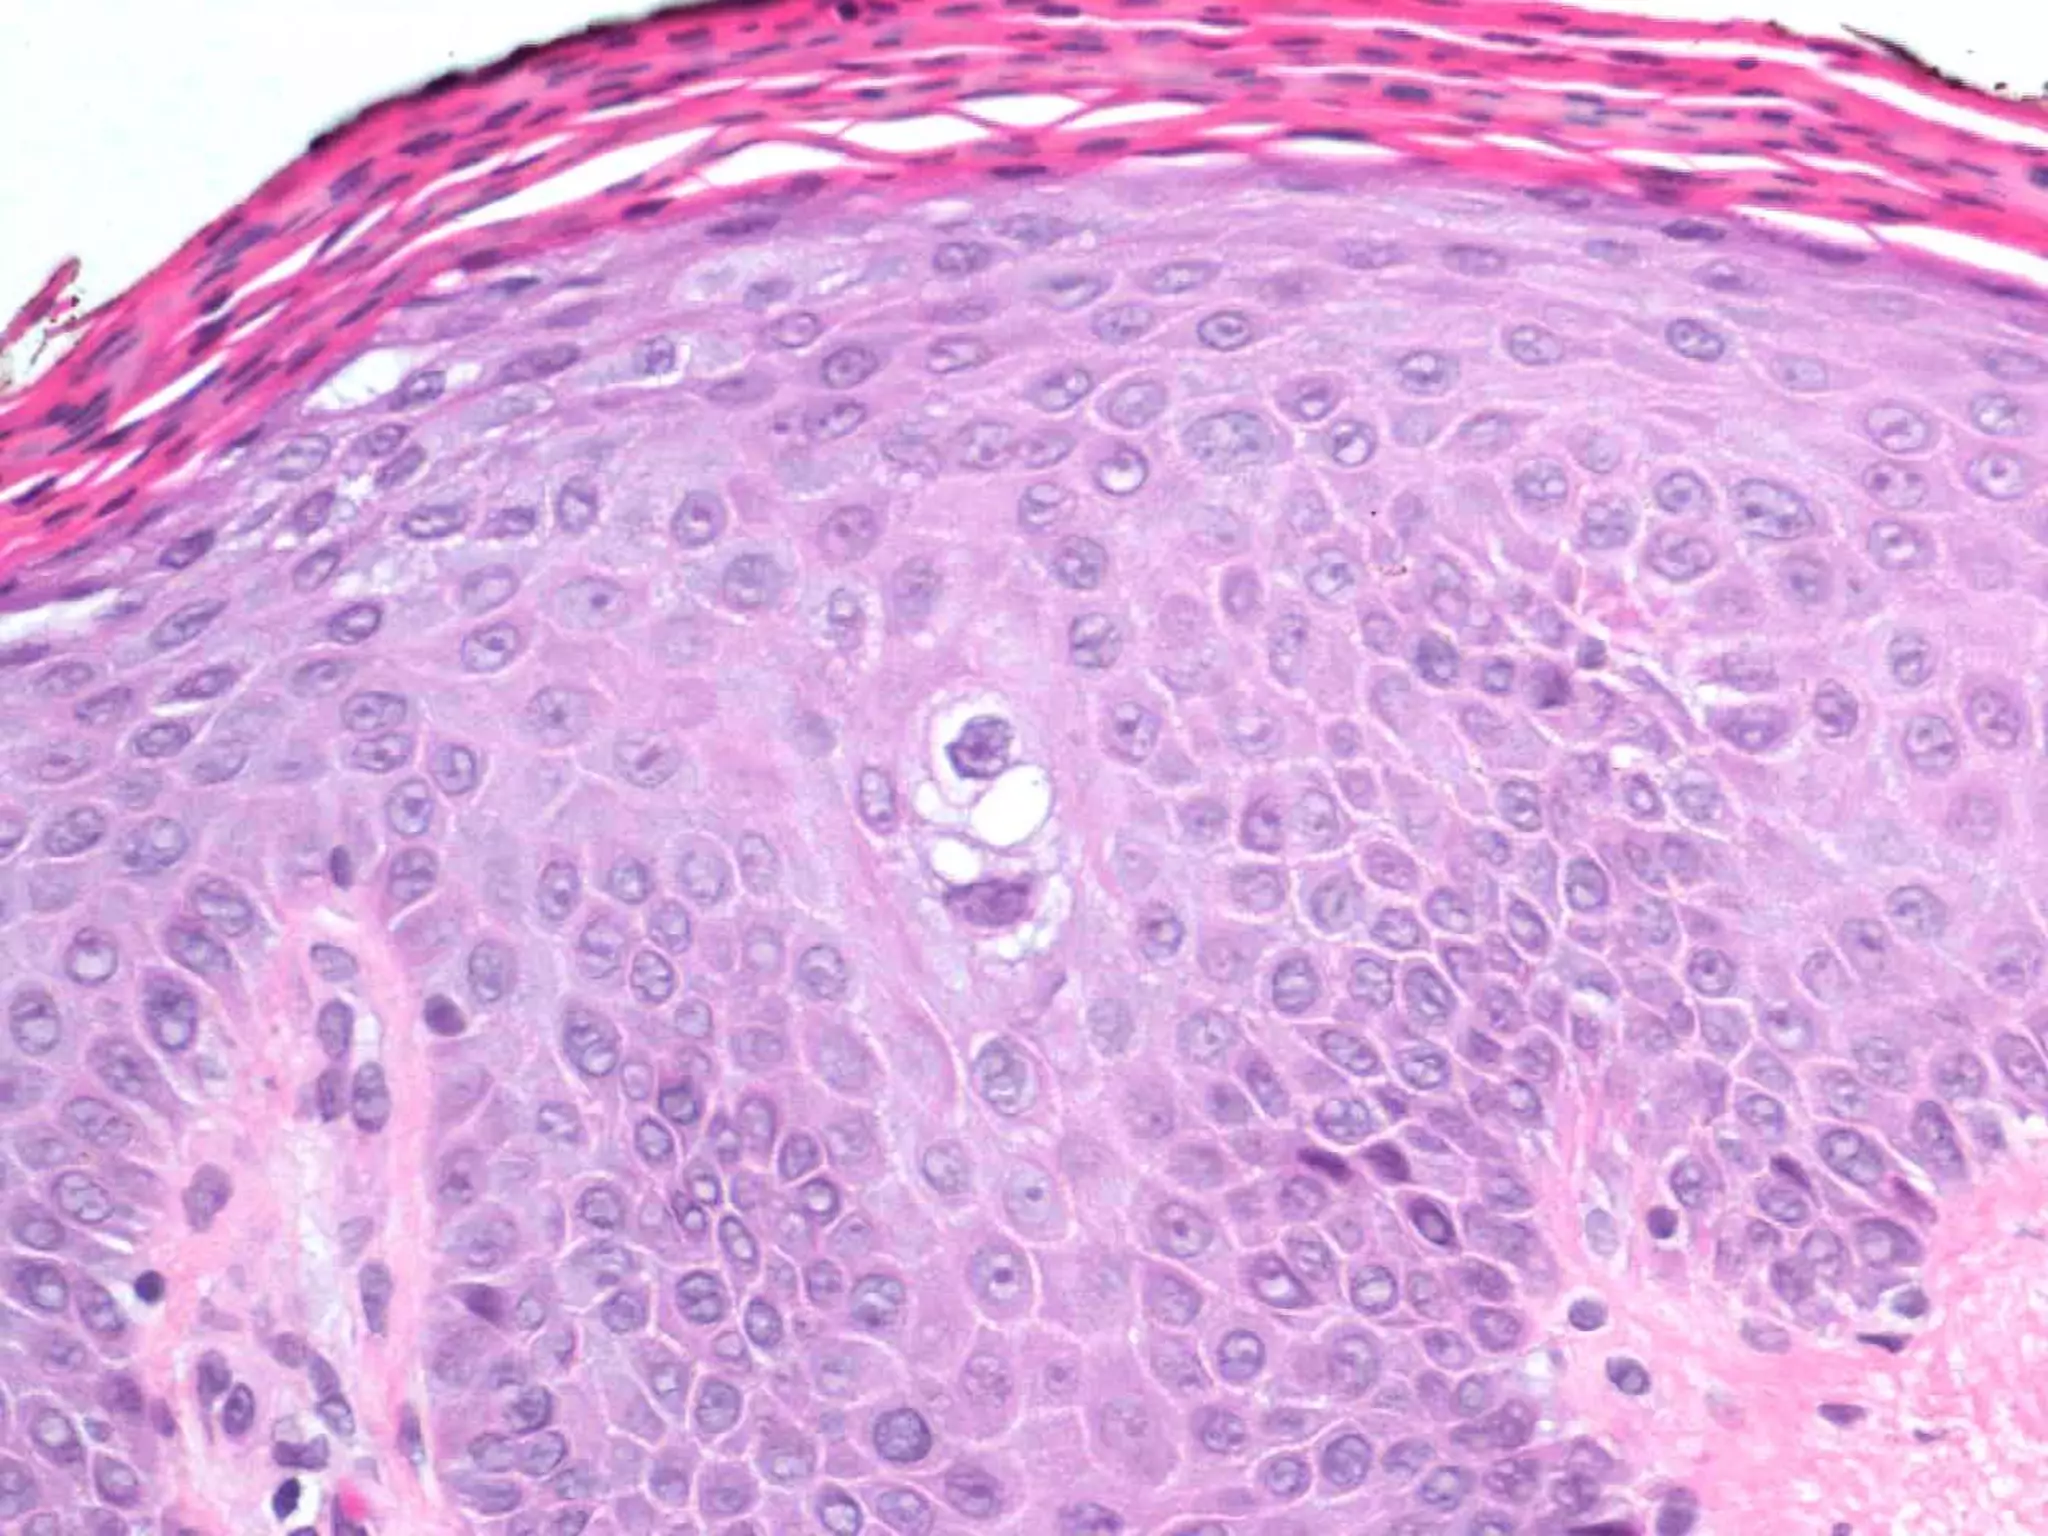

The document provides an overview of dermatopathology, including methods and techniques for skin biopsies such as shave, punch, and ellipse methods. It discusses key terms associated with dermatopathology, such as acantholysis and granulation tissue. Additionally, it references presentations by professionals in the field and essential dermatology resources.